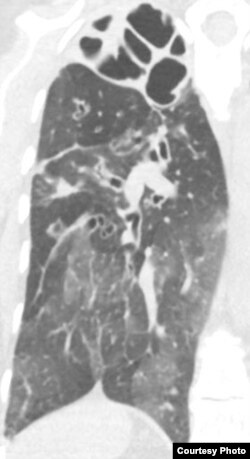

In this x-ray image, Pseudomonas infection in a lung is most visible at the top of the organ, which appears as a torn shroud over cavities. (Singh Lab, University of Washington)

“The key measure in cystic fibrosis and many lung diseases is forced expiratory volume, which is, you blow in a tube, and we see how much you can blow. And what we found is actually (forced expiratory volume) increased significantly from baseline in the realm of what we would normally see in an antibiotic-treated population. So, a similar effect as giving inhaled antibiotics or some oral antibiotics. And that was what I think made this an unusual finding, that the proof seemed to be there that you can give this drug intravenously, and it would actually impact lung function.”